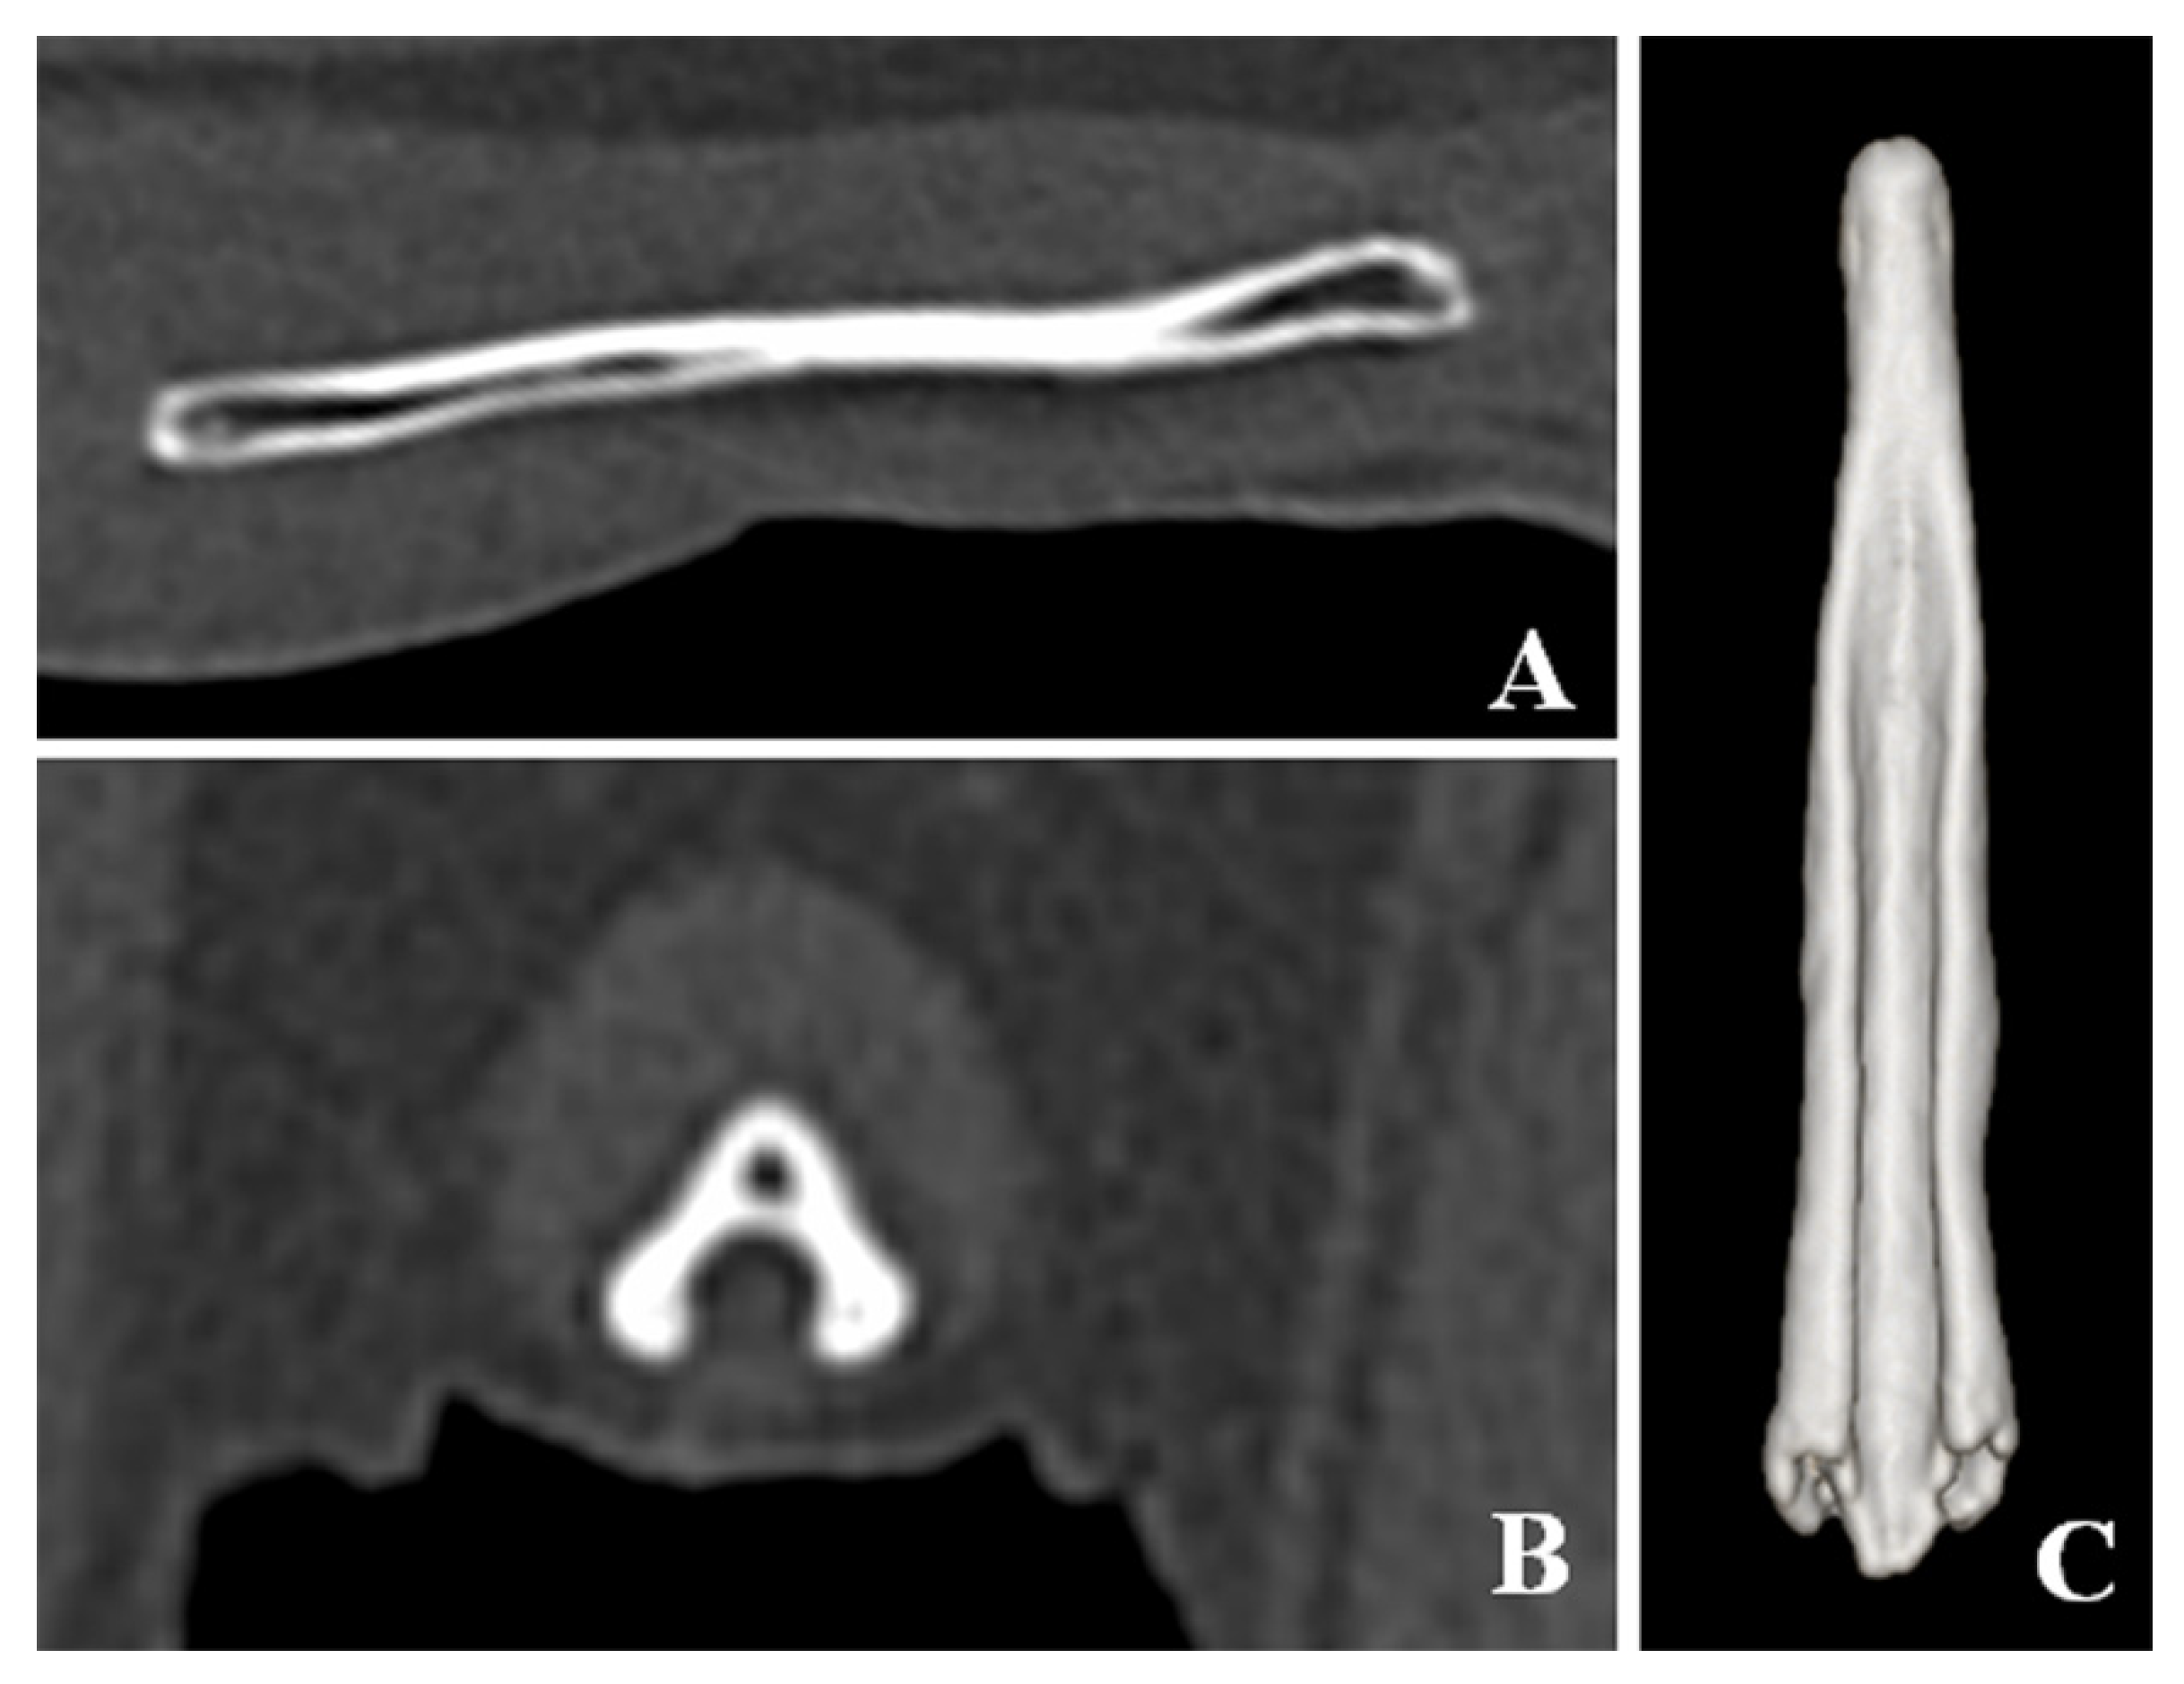

CT detected bladder calculi, urethritis, and proliferation of osseous tissue of the os penis. There was no calculus in the urethra. The normal ureteral groove of the dog was smooth (Figure 2); however, an arch of osseous tissues was formed around the urethra in the caudal portion of the baculum in this case (Figure 3A,C,D). The surface of the urethral groove was nodulous, with proliferation of osseous tissue (Figure 3A,B,D) in the central portion of the os penis. The arch was not formed in this region. In CT angiographic images, portosystemic shunt (left gastro-azygos shunt) was detected.

Figure 2. Computed tomographic images of the os penis in a normal dog. (A) Sagittal plane of the os penis. (B) Transverse plane of the os penis. (C) Ventral view of three-dimensional image of the os penis. The normal os penis is formed only by the urethral groove. The surface of the urethral groove is smooth.